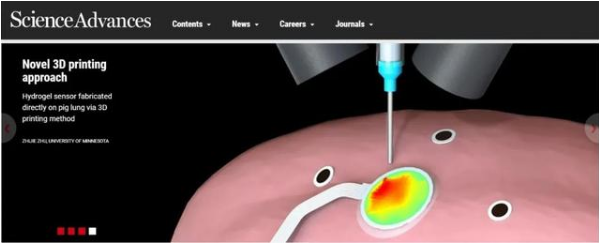

3D打印新成果!新技術或將助力診斷監測新冠肺炎

正如大家所知道的,在全球新冠肺炎爆發時期,3D打印技術用于打印防護口罩及面罩,極大的緩解了醫療資源的不足。最近3D打印技術在醫療領域又取得了一重大突破。由美國明尼蘇達大學的機械工程師和計算機科學家開發的一種新型3D打印技術登上了Science Advances期刊的封面,稱該技術或將用于新冠肺炎的診斷和檢測。我們熟知的傳統3D打印,是按照設計好的三維圖,一層一層的在靜止平臺上擠出熔融的材料,從而堆積成型。而這項研究,突破了3D打印靜止平臺的束縛,可將電子傳感器直接打印在正在擴張和收縮的器官表面上。研究小組的新技術通過使用雙攝像頭實時創建3D打印的工具路徑,精準控制打印位置。這種方法不僅可以被醫務人員用來在安全距離內監測傳染性患者,它甚至可以被用于診斷和監測感染COVID-19患者的肺部。下面我來給大家解釋一下這項突破性的3D打印技術的原理。實時3D表面跟蹤在這項研究中,研究人員將豬肺作為實驗對象,使用運動捕捉跟蹤標記方法,就像在電影中使用的那樣來創建特殊效果。這種方法是將視覺傳感系統與3D打印機集成在一起來跟蹤隨時間變化的3D幾何形狀,從而在可變形的肺部上制造電子柔性傳感器。過程分為兩個階段:1. 首先從預先掃描的數據集中離線學習了表面幾何圖形的低維參數模型,以降低后續在線計算的復雜度;2.在擠出機頭上安裝了兩個機器視覺攝像機,通過相機實時測量的一組標記來估計離線學習模型中的參數,從而在線調整了打印刀頭路徑的幾何形狀。EIT柔性傳感器費了這么大一番力氣打印在器官表面上的電子傳感器當然不一般。如下圖所示,這種電子柔性傳感器由離子水凝膠與EIT技術結合制成的,能夠檢測并監視器官的健康狀況。這項研究的第一作者,明尼蘇達大學機械工程學教授Michael McAlpine說:“我們正在以前所未有的新方式推動3D打印的界限,在移動物體上進行3D打印已經足夠困難,但是要找到一種在其膨脹和......